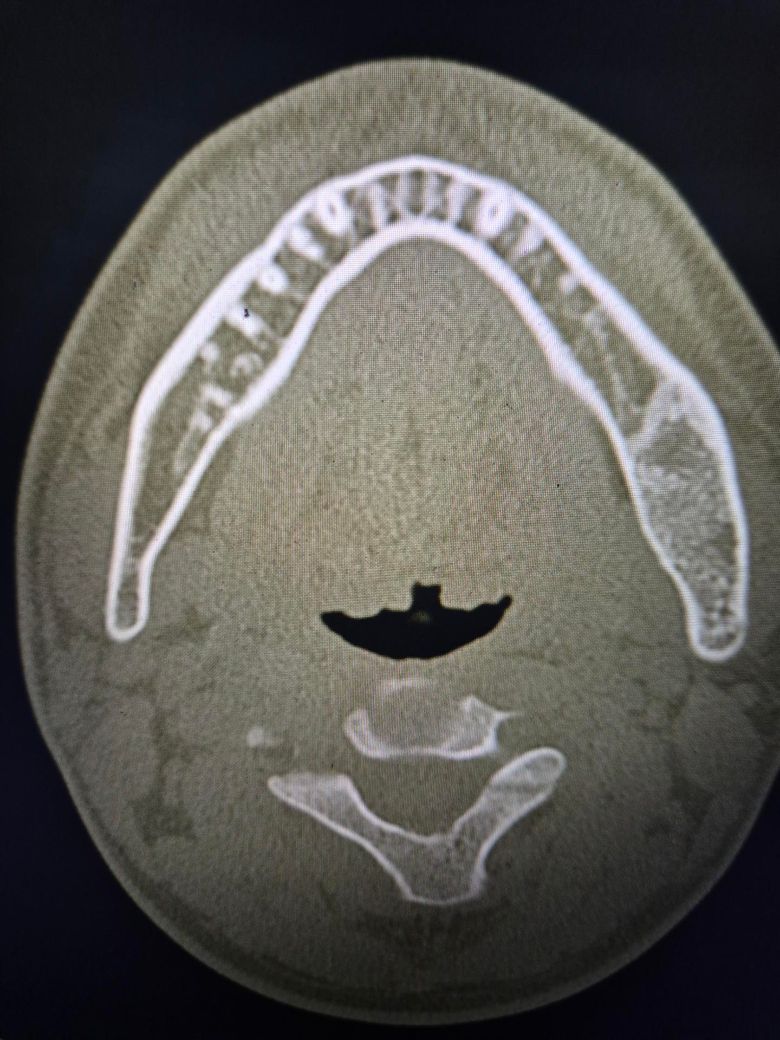

좌측 턱에 뭔가 있어서 질문드립니다.

치과에서 사랑니 빼다가 발견 한건데 저게 뭘까요?

뭔가 딱딱해 보인다고 들었던거 같은데, 콧구멍 쪽에도 있는거 같다는데 골종양 이런건가요?

• 3번 째 사진

엑스레이 상으로 크게 문제가 있어 보이는건 없습니다. 그냥 경화가 된부분이 보이는거 같습니다.

골육종 등 악성종양의 양상은 아닌 것으로 보입니다. 엑스레이 양상으론 fibrous dysplasia의 가능성이 있어보이나 정확한 진단은 대학병원 영상의학과 가보셔야 합니다.